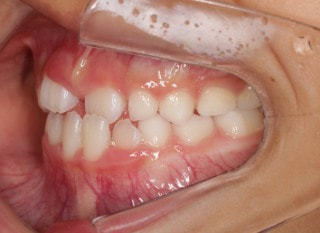

治療前

前歯装置装着時